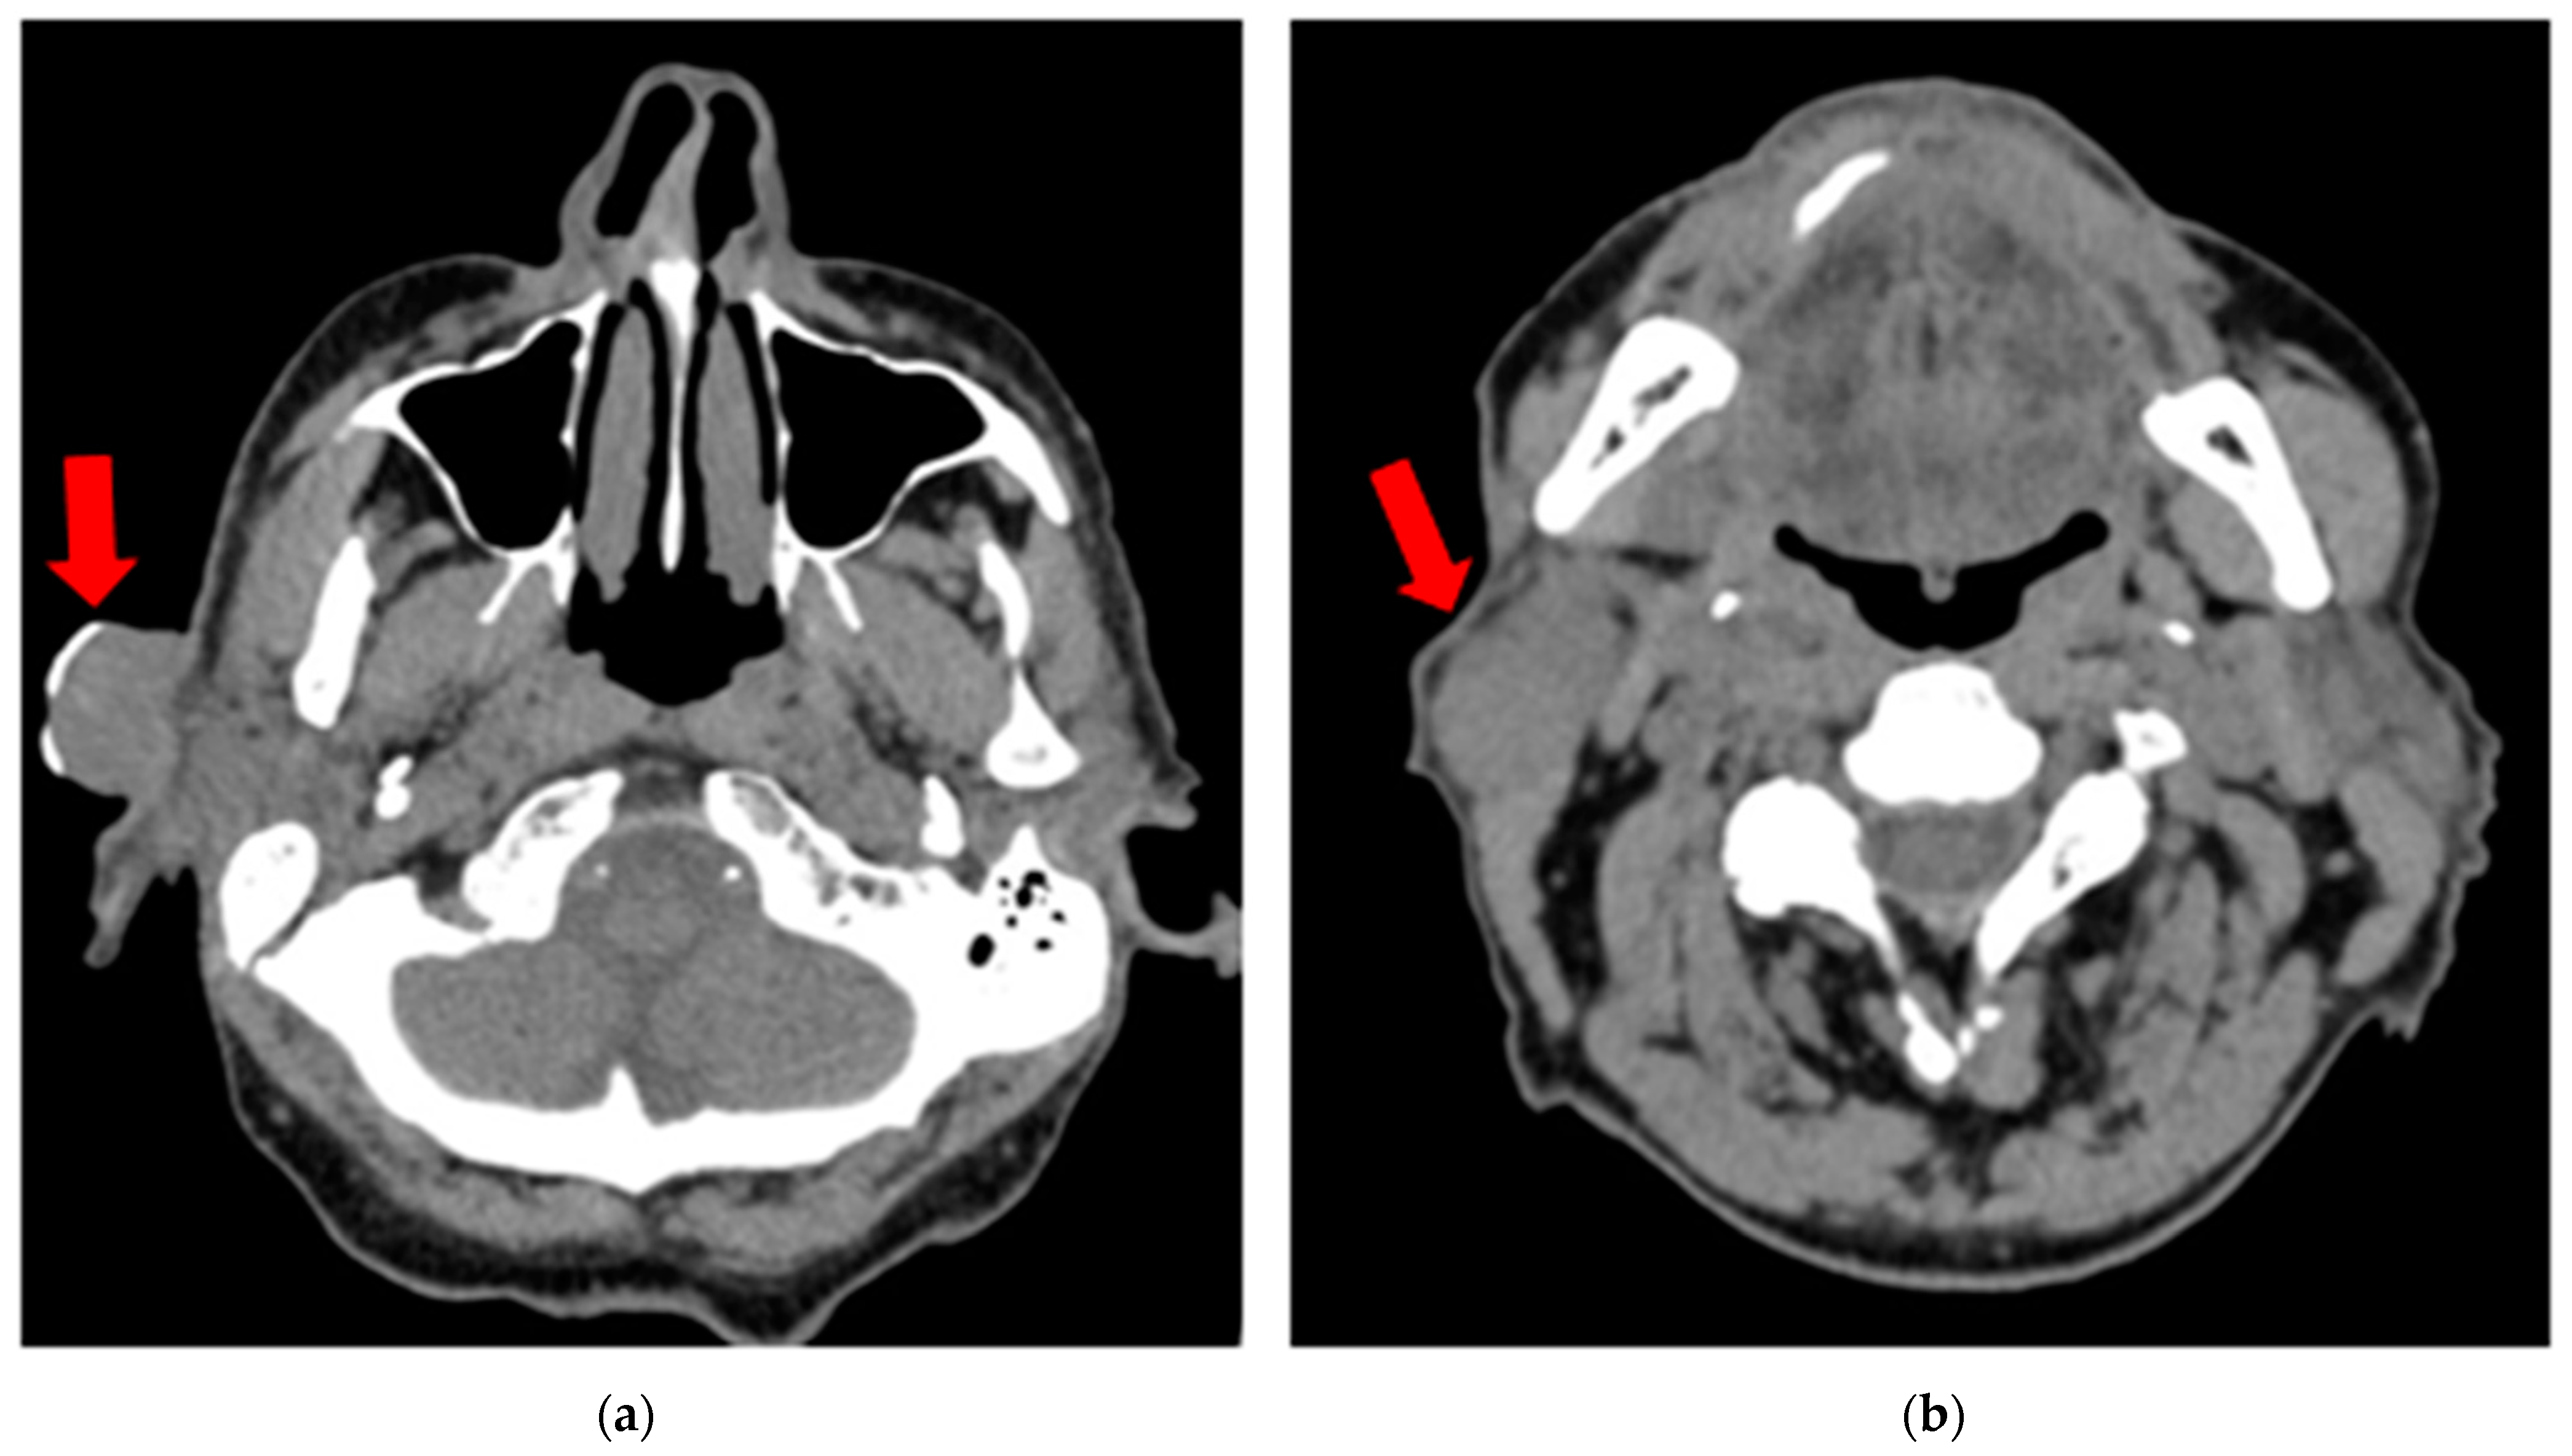

Due to ongoing renal insufficiency, a non-contrast CT scan was performed and showed a 26 × 21 mm exophytic tumor in the preauricular region and a 30 × 20 mm oval soft tissue lesion in the parotid tail anterior to the sternoclavicular muscle, suggestive of a metastatic node (Figure 2). There were no other enlarged nodes in the neck besides those noted. Distant metastases were excluded on chest and abdominal CT. After consultation with the tumor board, the patient was authorized for selective neck dissection at levels I–III with superficial parotidectomy and the excision of the cSCC.

Figure 2.

Non-contrast CT scan (vertical view) showing (a) a 26 × 21 mm exophytic tumor (cSCC) in the preauricular region (red arrow); (b) a 30 × 20 mm oval soft tissue lesion in the parotid tail anterior to the sternoclavicular muscle, suggestive of a metastatic node (red arrow).